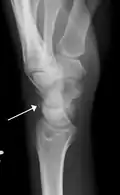

Triquetral fractures can occur due to forceful flexion of the wrist, causing an avulsion of the dorsal aspect of the bone that is often hidden on anterior radiographs, but can be seen as a tiny bone fragment on lateral views.

Triquetral fracture indicated by the white arrow. -

Triquetral fracture as seen on lateral view of a radiograph.